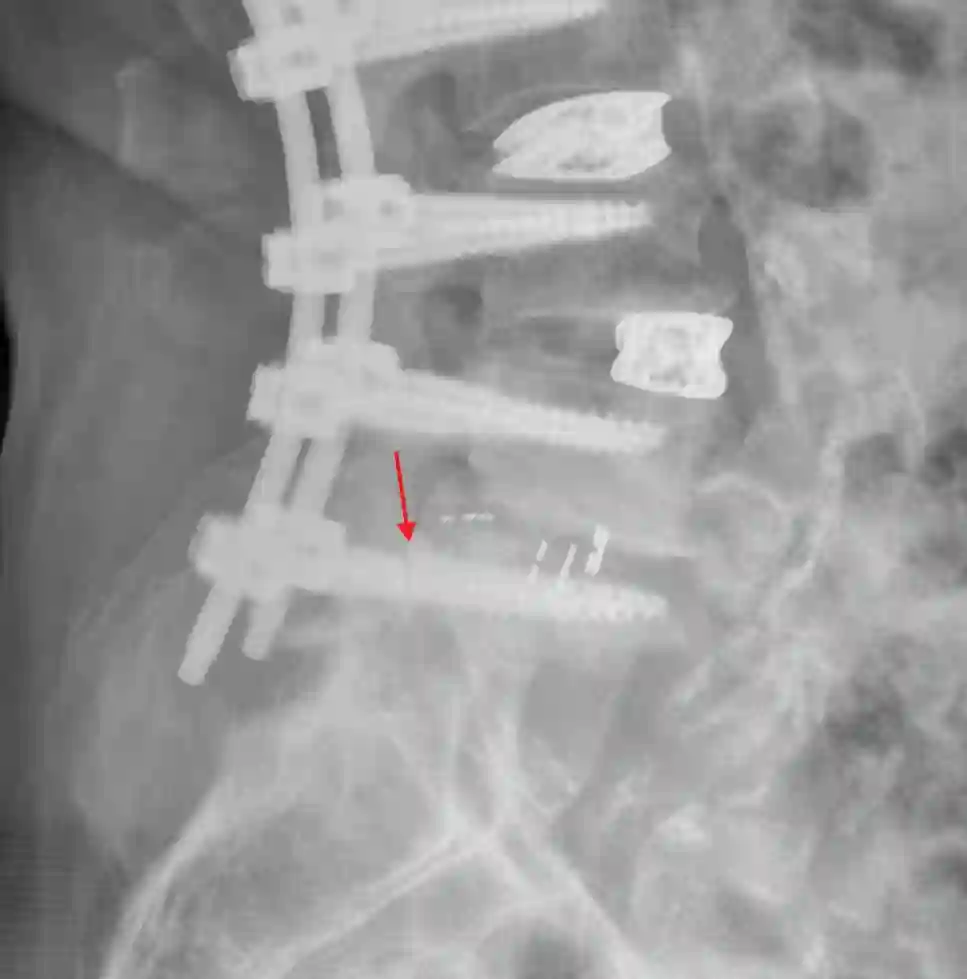

Herkömmliche Pedikelschrauben verursachen in der MRT Bildgebung Artefakte, sodass die MRT Bildgebung als suboptimal zur Beurteilung von Pedikelschrauben gilt. Der Goldstandard zur Lagebeurteilung von Pedikelschrauben ist die CT-Bildgebung.

Pedikelschraubenfehllage

Pedikelschraubenmigration

Als Pedikelschraubenmigration bezeichnet man das "wandern" der Pedikelschraube von der ursprünglichen Position.